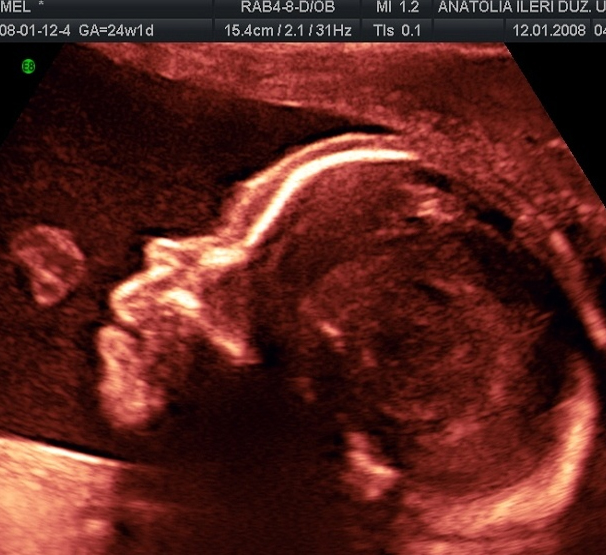

YÜZ PROFİL GÖRÜNTÜSÜ VE YUTKUNMA HAREKETİ